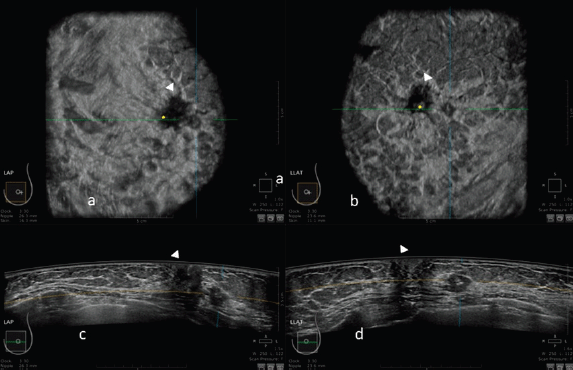

An example of the ABUS image is shown in Figure 1.

Figure 1. 3D ultrasound image at the dedicated workstation of a 82-year-old patient with biopsy proven ductal infiltrating carcinoma. a and b: reconstructed coronal plane; the lesion is marked as a reference point. Arrowhead shows the nipple. c and d: axial plane: the lesion is marked as a reference point. Arrowhead shows the nipple.